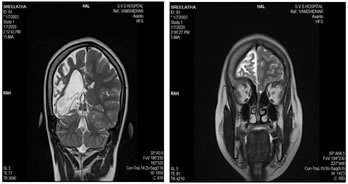

A 17-year-old female child was brought for deteriorated mental status and a history of few episodes of left focal seizures with secondary generalization since 2½ years. There was no history of head trauma. The seizure episodes were followed by decreased movement of the left side of the body and occasionally drooling of saliva from the left side. Perinatal vs. birth history was uneventful. The patient did not attend school. On examination, the child was undernourished with very poor cognitive function. Vitals were normal. Positive clinical findings noted were – microcephaly, severe mental retardation with an intelligence quotient of 40 and left-sided facial palsy. Examination of the central nervous system revealed left hemiparesis. Examination of other systems was unremarkable. Radiographs of skull showed thickening of the right hemicalvarium [Figure 1]. Non-contrast computed tomography and magnetic resonance imaging (MRI) reveled unilateral atrophy of the right cerebral hemisphere and ex- vacuo dilatation of ipsilateral lateral ventricle with prominence of sulci [Figures 2 and 3]. Thickening of the right hemicalvarium was noted measuring 7-8 mm compared to 5 mm on the left side (in frontal region at level of lateral ventricles) and enlarged right frontal sinus. These findings were suggestive of DDMS.

Figure 1: Skull radiographs: Anterioposterior and lateral views showing thickening of the right hemicalvarium (asterisk *); Figure 2: Axial sections of non-contrast magnetic resonance imaging (T1) and computed tomography (brain window) of the brain showing diffuse atrophy of the right cerebral hemisphere with ex-vacuo dilatation of the right lateral ventricle and prominence of sulci over the right cerebral hemisphere. Compensatory thickening of the right hemicalvarium is also seen; Figure 3: Coronal (T2) Magnetic resonance imaging and axial computed tomography(bone window) of the brain showing diffuse atrophy of the right cerebral hemisphere with ex-vacuo dilatation of the right lateral ventricle and compensatory thickening of the right hemicalvarium